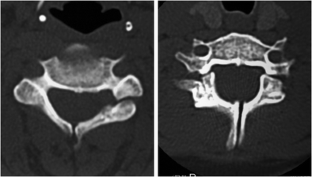

Atypical, unusual, and misleading imaging presentations of spondylolysis

Although lumbar spondylolysis is a widely known and easily recognizable condition in its typical presentation, there are some less well-known forms that may occasionally be challenging and/or demand special attention on imaging. Examples include: acute and/or incomplete lesions; unilateral defects; lesions at unusual levels (cervical, upper lumbar, and multi-level spondylolyses); iatrogenic lesions; non-isthmic spondylolysis; and spondylolysis related to underlying diseases. In addition to their atypical, uncommon or confusing imaging presentations, these forms of spondylolysis are far rarer than the classic type and have been described, to a great extent, in the surgical literature, thus reducing the awareness of radiologists about them and raising the potential for misdiagnosis and inadequate treatment. In this review the authors address these special manifestations of spondylolysis, stressing the more important features to be considered in the differential diagnosis and the impact of a precise diagnosis of spondylolysis on the patient’s care.